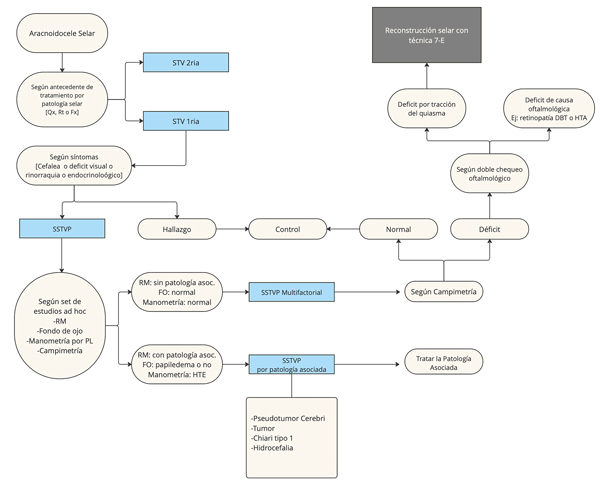

En enero de 2020 nuestro equipo elaboró un algoritmo preliminar para la selección de pacientes quirúrgicos con STV (Figura 1).

Figura 1. Algoritmo preliminar para la selección de pacientes candidatos a reconstrucción del piso selar por SSTVP. FO: fondo de ojo. HTE: Hipertensión endocraneana. PL: punción lumbar. RM: Resonancia magnética. SSTVP: Síndrome de silla turca vacía primaria. STV: Silla turca vacía.